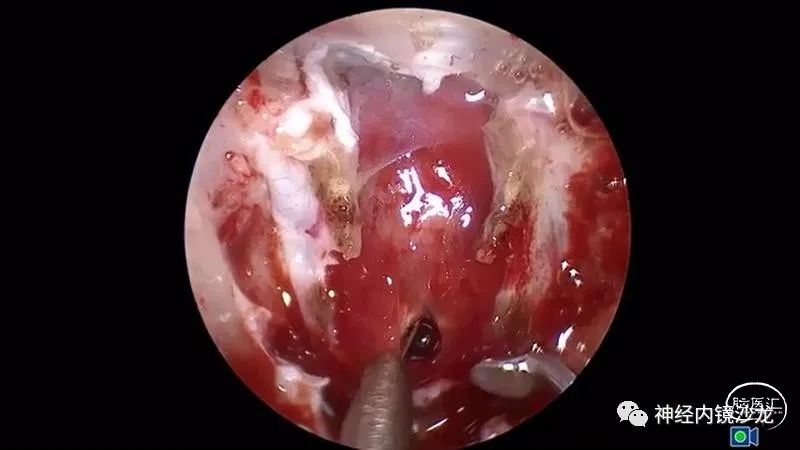

手术暴露充分术野,从蝶骨平台到斜坡,从眼眶到眼眶。切除大块钙化部分肿瘤后,我们找到肿瘤包膜和下丘脑、视觉通路之间的清晰的分离平面。切除结束时,发生了后交通动脉从大脑后动脉撕脱导致的动脉出血。采用单轴持夹器放置一个成角的动脉瘤夹,以夹闭损伤部位并保证供血动脉不狭窄。术后即刻和晚期磁共振成像和CTA检查显示肿瘤全切、无卒中、无假性动脉瘤形成。